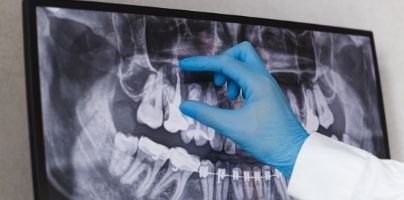

OPG

An OPG (Orthopantomagram) is a panoramic scanning dental X-ray of the upper and lower jaw. It is also sometimes called Orthopantomagraph or by the proprietary name Panorex. It shows a flattened two-dimensional view of a half-circle from ear to ear.